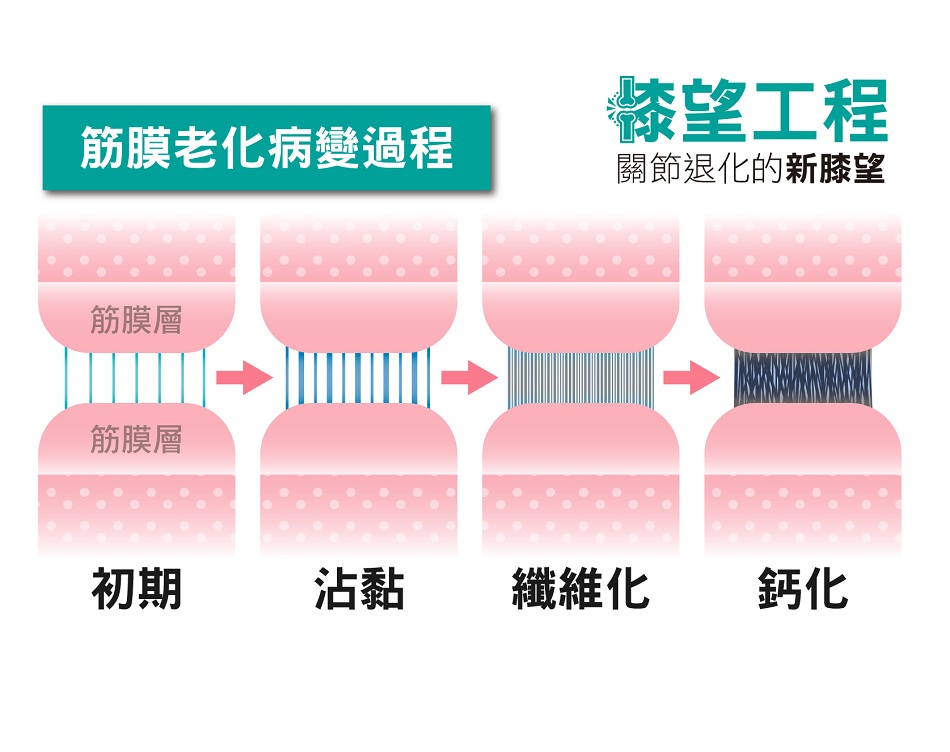

筋膜系統在長時間處於壓力過大或不平衡狀態下,便無法正常將細胞內的不良代謝物順利排出,不良代謝物持續在筋膜層堆疊累積造成發炎,最終形成筋膜沾黏、鈣化、纖維化等現象,進而造成病患的疼痛與各種不適反應。